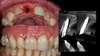

Gestion Mucco-Gingivale péri-implantaire

La ceinture de gencive kératinisée est la seule garantie au long cours de la pérennité de nos implants, elle est également importante pour la gestion de l’équilibre du rose et du blanc. Le prélèvement de conjonctif tubérositaire présente toutes les qualités particulières pour l’assurer.